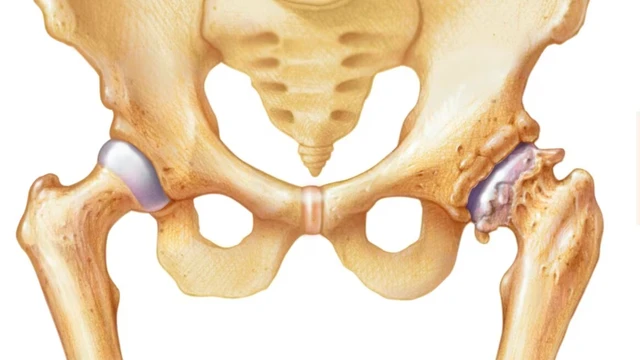

Hẹp khe khớp háng có thể được phát hiện trên hình ảnh X-quang. Ở một khớp khỏe mạnh, có một khoảng trống bình thường giữa các đầu xương tạo thành ổ khớp. Các đầu xương trong khớp được bao phủ bởi sụn khớp. Ở một khớp không khỏe mạnh (bị ảnh hưởng bởi các tình trạng gây viêm khớp) có bằng chứng về sự thu hẹp khoảng cách giữa các đầu xương trong khớp (hẹp khe khớp) do mất sụn.